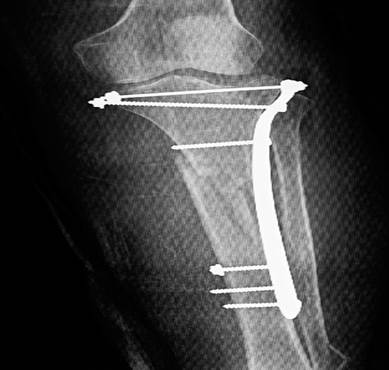

Una vez en el quirófano, se comenzó con la reducción de la meseta tibial con perno de Web y luego se utilizó lámina subcutánea para tornillos convencionales y bloqueados de 4,5 milímetros, desde la meseta tibial hasta las uniones del tercio medio e inferior de la tibia. El dispositivo de osteosíntesis se colocó a través de dos abordajes quirúrgicos, para evitar toda la exposición de los tercios proximales y distales de la tibia. La reducción fue corroborada mediante fluoroscopia con intensificador de imágenes (Figura 2).